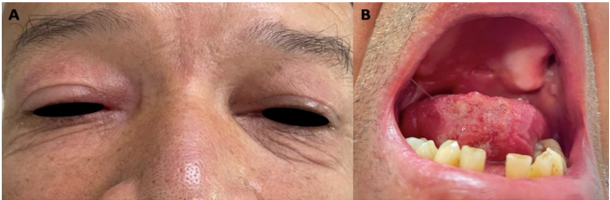

En el seguimiento a los dos meses se observa grata mejoría de las lesiones granulomatosas a nivel de OD y lengua, no obstante, aún con persistencia de éstas (Fig. 2a y b), por otra parte, en el examen físico a la palpación se detecta en cuadrante superior abdominal una masa, asociado a signos de dificultad respiratoria, por lo que se solicita ecografía abdominal total y radiografía de tórax, y una Resonancia Magnética de cráneo (RNM) por prurito en OD, y para el seguimiento del manejo medicamentoso con itraconazol se decide evaluar función hepática, solicitar Alanina transaminasa (ALT), Aspartato transaminasa (AST), Bilirrubina Directa (BD), Bilirrubina Indirecta (BI) y Fosfatasa Alcalina (FA).